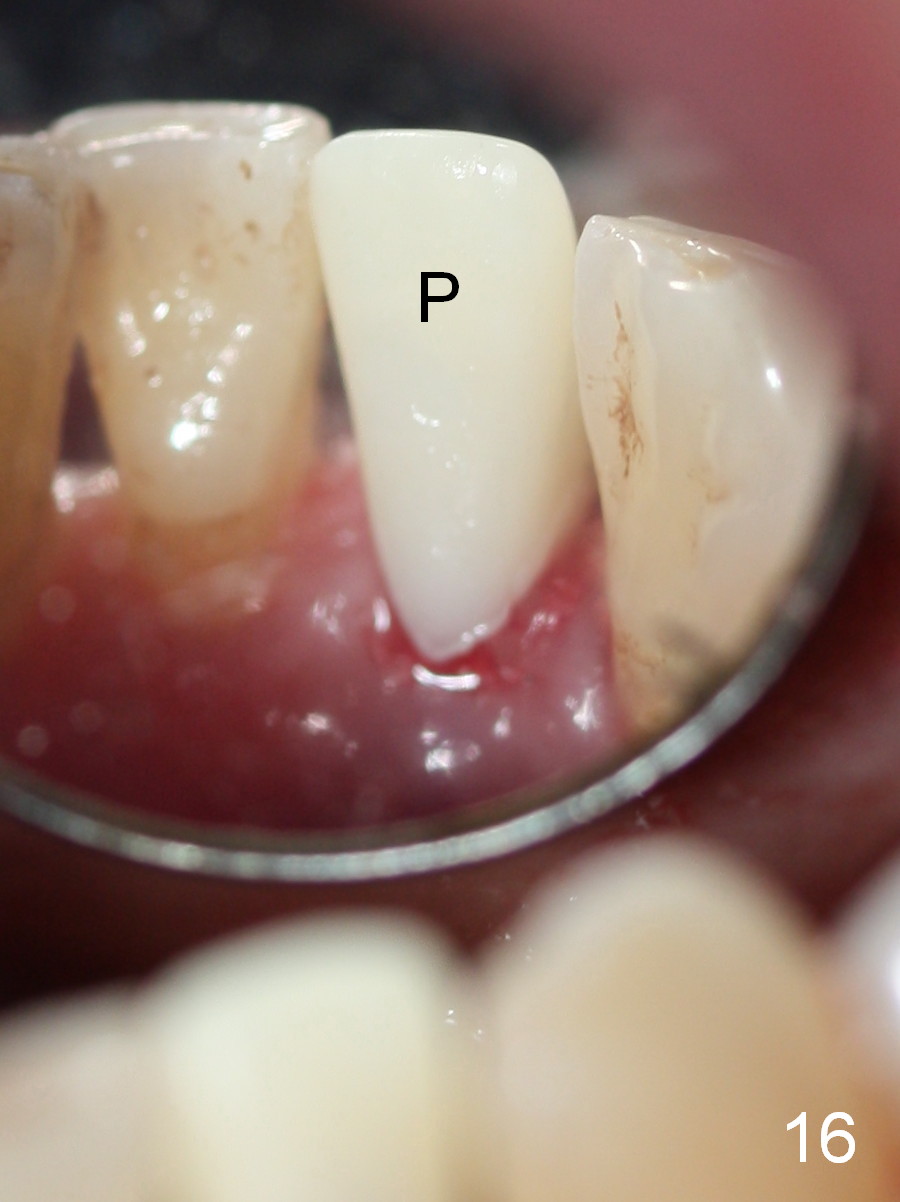

A 74-year-old man has several missing teeth (Fig.1). His 1st goal is to replace the lower left lateral incisor (Fig.2). The residual root has an apical lesion (Fig.3 *). To describe intraop findings, a CT image of a different patient is used (Fig.4 coronal section; B: buccal; L: lingual). After extraction, the buccal plate is found to be thin and low (Fig.5 arrowheads). A 1.5 mm pilot drill (Fig.6 red line) is used to initiate osteotomy in the lingual plate of the socket. Once the drill penetrates the lingual plate, the trajectory changes and the depth is 17 mm from the gingival margin (Fig.7). A PA is taken (Fig.8); it appears that the osteotomy can be extended more apically. When the pilot drill extends to 20 mm, there is sudden empty feeling. The lingual plate has perforated (Fig.9). A new osteotomy is established buccally (Fig.10 pink). To avoid buccal plate perforation, especially in the buccal undercut area (>), the coronal end of the drill has to be tilted buccally (<--). An angled abutment (3x20 mm, 15°) is placed (Fig.11,12). The abutment is modified (Fig.13,14) to accommodate an immediate provisional (Fig.15,16 P). Perio dressing is to be applied to prevent the bone graft from getting dislodged buccally (Fig.15). The dressing is in place 7 days postop (Fig.17).

Five months postop, the peri-implant space reduces (Fig.18). A keratinized band forms buccal to the implant (Fig.19 *). The provisional dislodges probably due to the buccal placement (Fig.20).